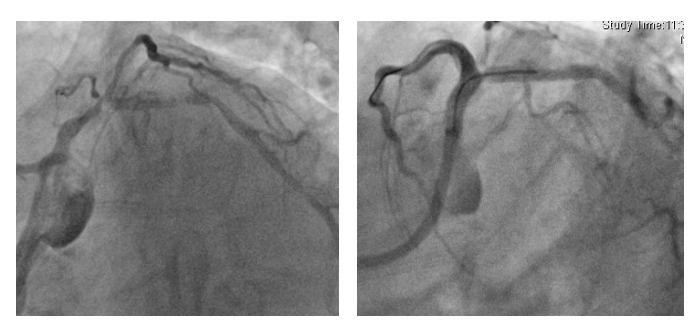

近日,一位68岁的老年男性患者,因“脑梗死后三年,出现头晕,行走不稳”就诊于我院神经内科,行颅脑CTA提示多发颅内大血管狭窄,为进一步诊治收入院。同时该患者有高血压病史20余年,冠心病,劳力型心绞痛病史近10年,虽然平素服用单硝酸异山梨酯、地尔硫卓等药物,但冠心病控制不佳,心绞痛仍时有发作。患者入院后,神经内科张小峰主治医师为该患者完善了全脑动脉造影,提示患者左侧椎动脉开口重度狭窄,这正是引起患者头晕症状的主要原因,但张医师并没有盲目为患者实施介入治疗,而是结合患者病史以及入院后的辅助检查结果,认为该患者可能同时存在脑血管,冠状动脉等多部位粥样硬化斑块及血管狭窄,为了减少患者痛苦,经与心脏内科薛亚军医师会诊共同商讨后,决定由两科介入团队联合完成冠状动脉和脑血管造影检查,一次性完成心脑血管评估,并同步开展脑血管介入诊疗及冠心病介入诊疗。经过充分准备后,2019年6月20日,神经内科张小峰医师带领王也医师及其介入团队通过股动脉途径,首先为患者顺利完成左侧椎动脉起始部位狭窄病变的介入治疗,植入一枚支架,保证了脑灌注(如图1)。随后心脏内科介入团队,在王伟民教授带领下,薛亚军与缪国斌医生通过神经内科已经建立的股动脉通路,为患者顺利完成冠状动脉造影,结果提示患者冠状动脉病变极其严重,医学上称为“左主干+三支冠脉病变”,如果不及时处理,随时有生命风险,王伟民教授果断为患者实施了左主干、前降支及回旋支分叉病变的介入治疗,并植入支架,顺利开通了闭塞的血管(如图2),挽救这位患者岌岌可危的心脏,整个介入手术过程耗时不足2小时,患者清醒,无任何痛苦,术后仅在腹股沟处留有一个约米粒大小的穿刺点,术后6小时就能够坐起并下地活动,真正体现了微创、快速、安全及准确的救治理念。5天后,心脏内科又经桡动脉为其完成右冠脉的介入治疗,彻底解决患者多年来的“心”病,经过两科室的联合精心救治,患者于2019年6月28日康复出院。出院时患者对我院的整个治疗过称给予了高度的评价,并表示了真挚的感谢(图3)。

图2 心脏内科对患者冠状动脉左主干+前降支+回旋支介入治疗前后对比(左图术前,右图术后)